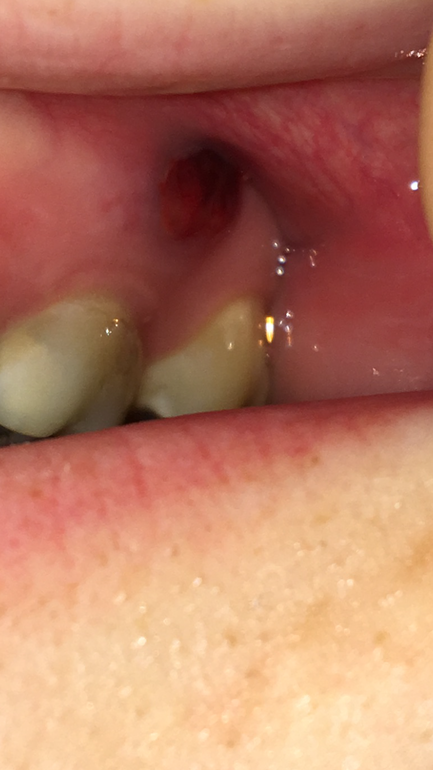

Год назад запломбировала зуб, врач сохранил нервы, но пошла реакция на материал и появился свищ на десне, три дня назад открыли зуб, почистили каналы, оставили на несколько дней, сейчас полоскаю рот, только что заметила, что место где он был - почернело! И как будто плёночка с него сдерлась, немного кровит!

Что это такое? 😭😭😭 к врачу только в понедельник, место свища не беспокоит, не болит.

Раньше там был мешочек с гноем🤢, он был желтый но не черный/синий/фиолетовый

Ну и нормально, что свищевой ход потемнел. Полость опорожнилась, процесс отторжения клеток, которые отмерли запустился, заодно начали нарастать новые грануляции, ткань поэтому и изменила цвет. На данный момент на фото нет никакого криминала.

почему вокруг свища темное кольцо?😖